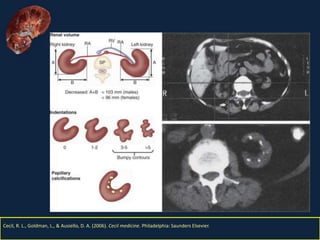

El documento resume la nefritis tubulointersticial, una enfermedad renal inflamatoria que causa daño en los túbulos y el intersticio renal. Puede ser aguda o crónica, siendo la aguda generalmente inducida por fármacos e infecciones y caracterizada por edema e inflamación, mientras que la crónica se caracteriza por fibrosis intersticial, atrofia y fibrosis tubular. El daño tubulointersticial conduce a la falla de la función renal.